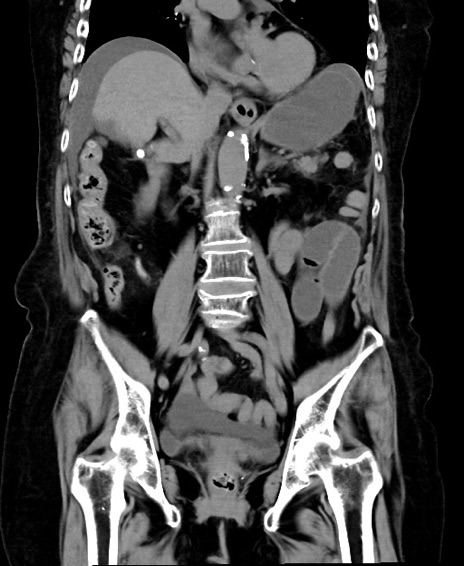

横断像